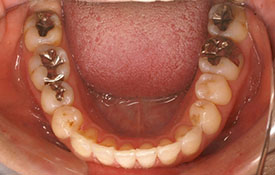

インビザラインの治療例:CASE-2

| プロフィール | 15歳 男性 |

| 所見 | アメリカから転院されて来られた方です。 インビザラインで上下顎の矯正治療を開始し下顎はアメリカで終了しており、上顎のみ治療の後期を担当しました。 アイライナーの装着は、1日平均22時間ほどでした。 |